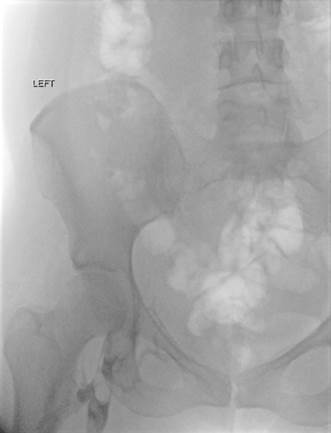

Venograma de la pierna izquierda donde se muestra un trombo oclusivo en las venas profundas más visualizadas.